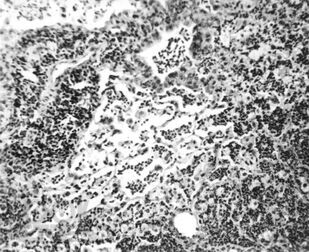

Книга посвящена вопросу лечения пелоидами очень распространенной патологии – болезней органов дыхания: острой пневмонии, хронического бронхита, бронхиальной астмы. В эксперименте и на клиническом материале показано воздействие грязелечения на воспалительный процесс, состояние иммунитета и адаптации, бронхиальную проходимость. Дана эффективность назначения иловых сульфидных, сапропелевых грязей и торфов у больных с болезнями органов дыхания. Рассмотрены вопросы переносимости этими больными грязелечения и возможности оптимизации его результатов. Приведены материалы по использованию средства «Тонус плюс», сочетающего в себе биологически активные компоненты двух видов грязей, набора трав и солевых носителей. Книга предназначена для физиотерапевтов, курортологов, пульмонологов, врачей общей практики. Это первый обобщенный труд по использованию грязелечения в пульмонологии. Его данные могут быть использованы не только в практической работе врачей, но и в учебном процессе при подготовке физиотерапевтов и курортологов.